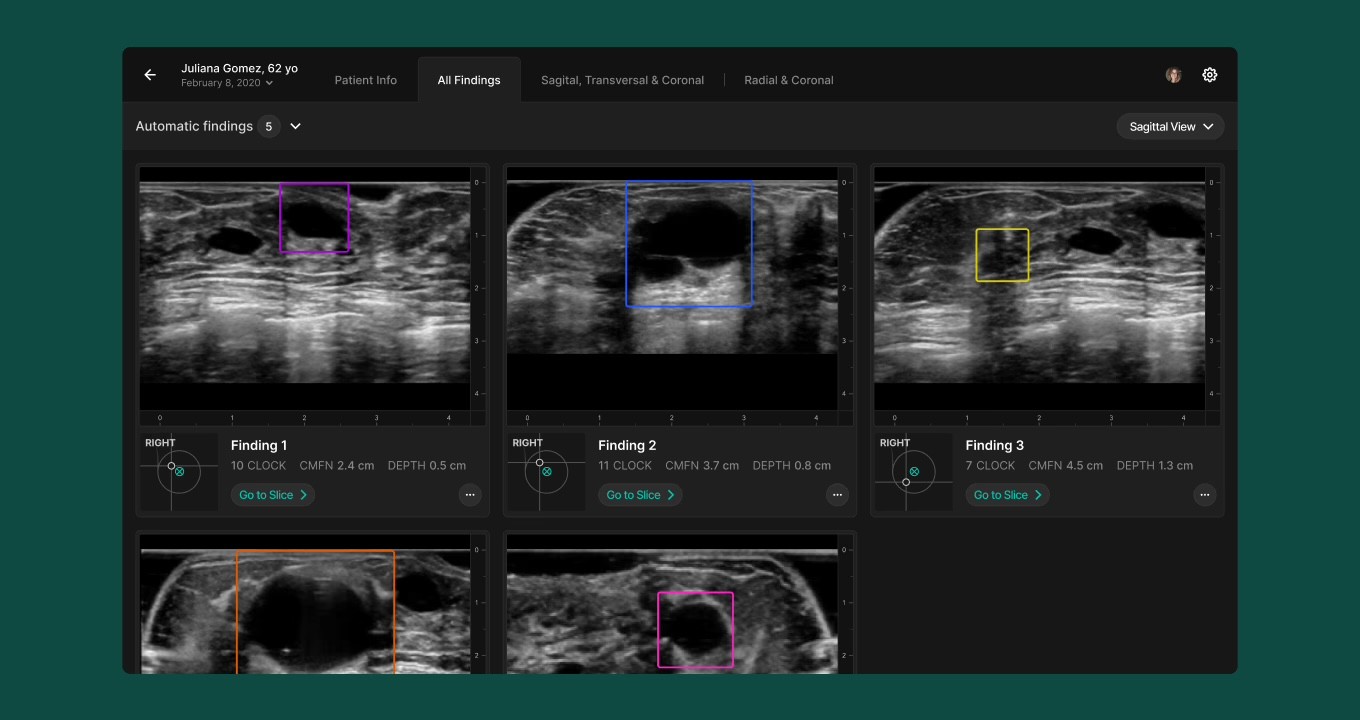

In UX/UI, we redesigned the review interface to surface only the most relevant 3D images (those flagged by AI), with an option to expand into a multi-plane comparison mode. The redesigned Scrubber allows radiologists to navigate slices quickly and correlate findings across planes, improving interpretation speed and clarity.

Refined the Radiologist Experience

Designed a new interface that surfaces AI-flagged 3D images first, reducing the number of slices to review and easing cognitive load.